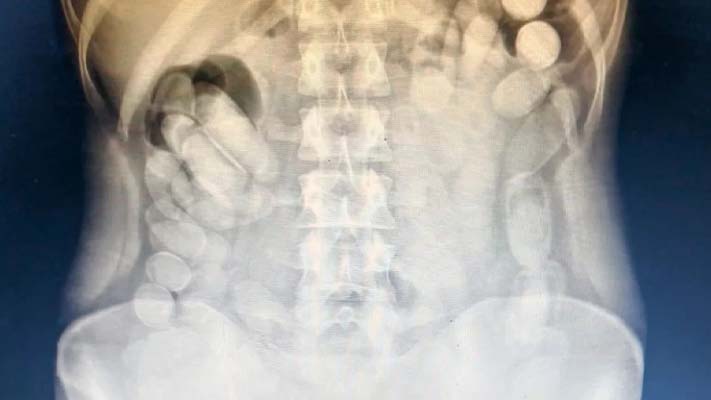

Detienen a una pasajera que había ingerido más de 100 cápsulas de cocaína

18/06/2025 Efectivos del Escuadrón 55 “Tucumán” realizaban tareas de prevención y de seguridad vial sobre la Ruta Nacional Nº 9, a la altura del Kilómetro 1.358 en el Peaje “Molle Yaco”, y detuvieron la marcha de un transporte público de pasajeros. Al realizar la inspección, detectaron que una de las pasajeras poseía 12 cápsulas (con una […]